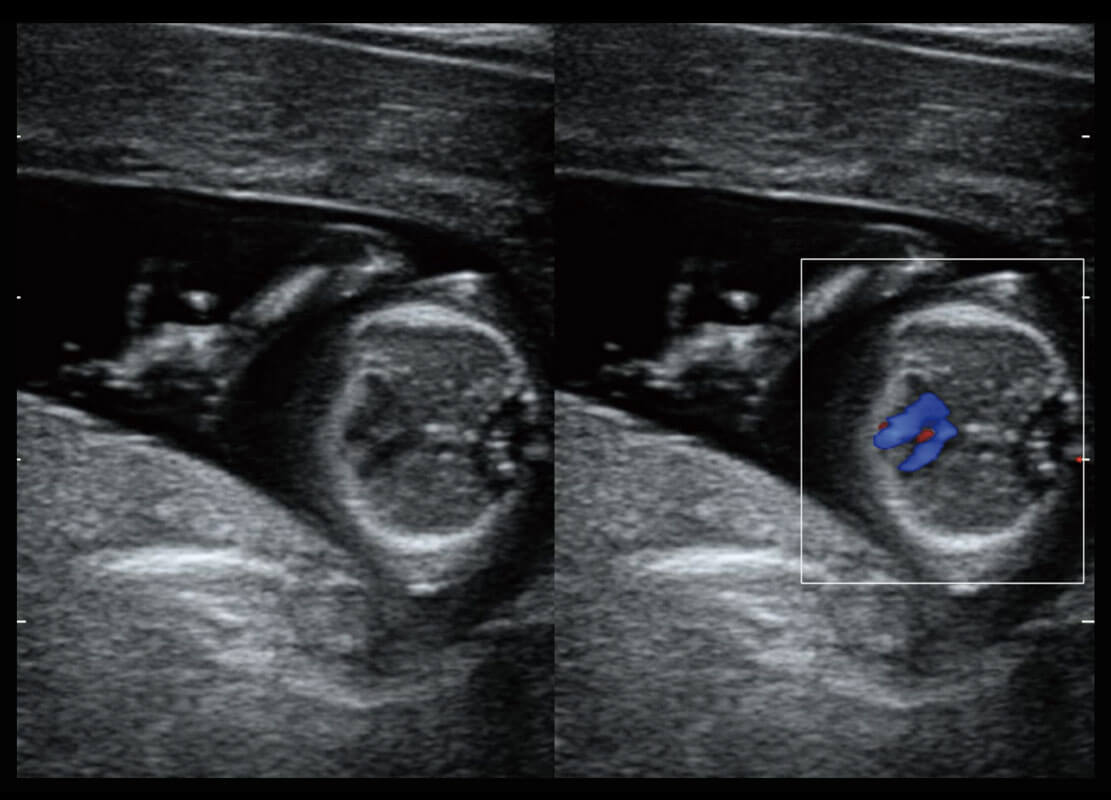

P60搭载一系列胎儿心脏成像技术,实现精细的胎儿心脏评估。

四腔切面

四腔心血流

胎心容积成像